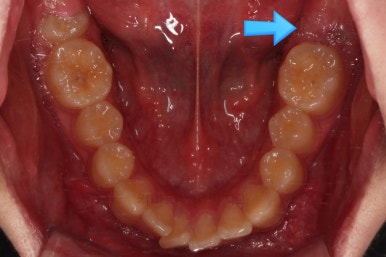

초진 때의 입안의 모습입니다.

대신, 우측 아래 사진 화살표를 보시면 나와야 될 어금니가 나오지 못하고 있는 상황이었어요.